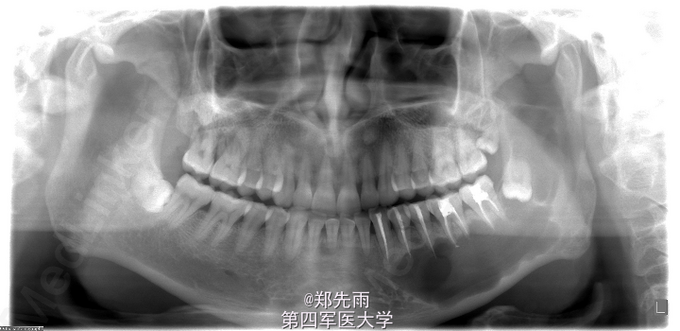

左侧下颌骨角化囊性瘤保守治疗

左侧下颌骨区肿胀不适伴张口受限1月余,外院拍片提示左侧下颌体部及升支部囊性病变,遂来我院

张口度2横指,左侧下颌角部肿胀明显,颊舌侧未及明显膨隆,左下唇无麻木。

诊断:左侧下颌囊性病变,考虑角化囊性瘤及成釉细胞瘤。 处理:行术前累积牙根管治疗,术中行刮治术+术中冰冻,提示角化囊性瘤,予以医用硫酸钙充填囊腔。

随访期间患者无感染等不适,鉴于硫酸钙植入术后患者易肿胀,建议密切随访。